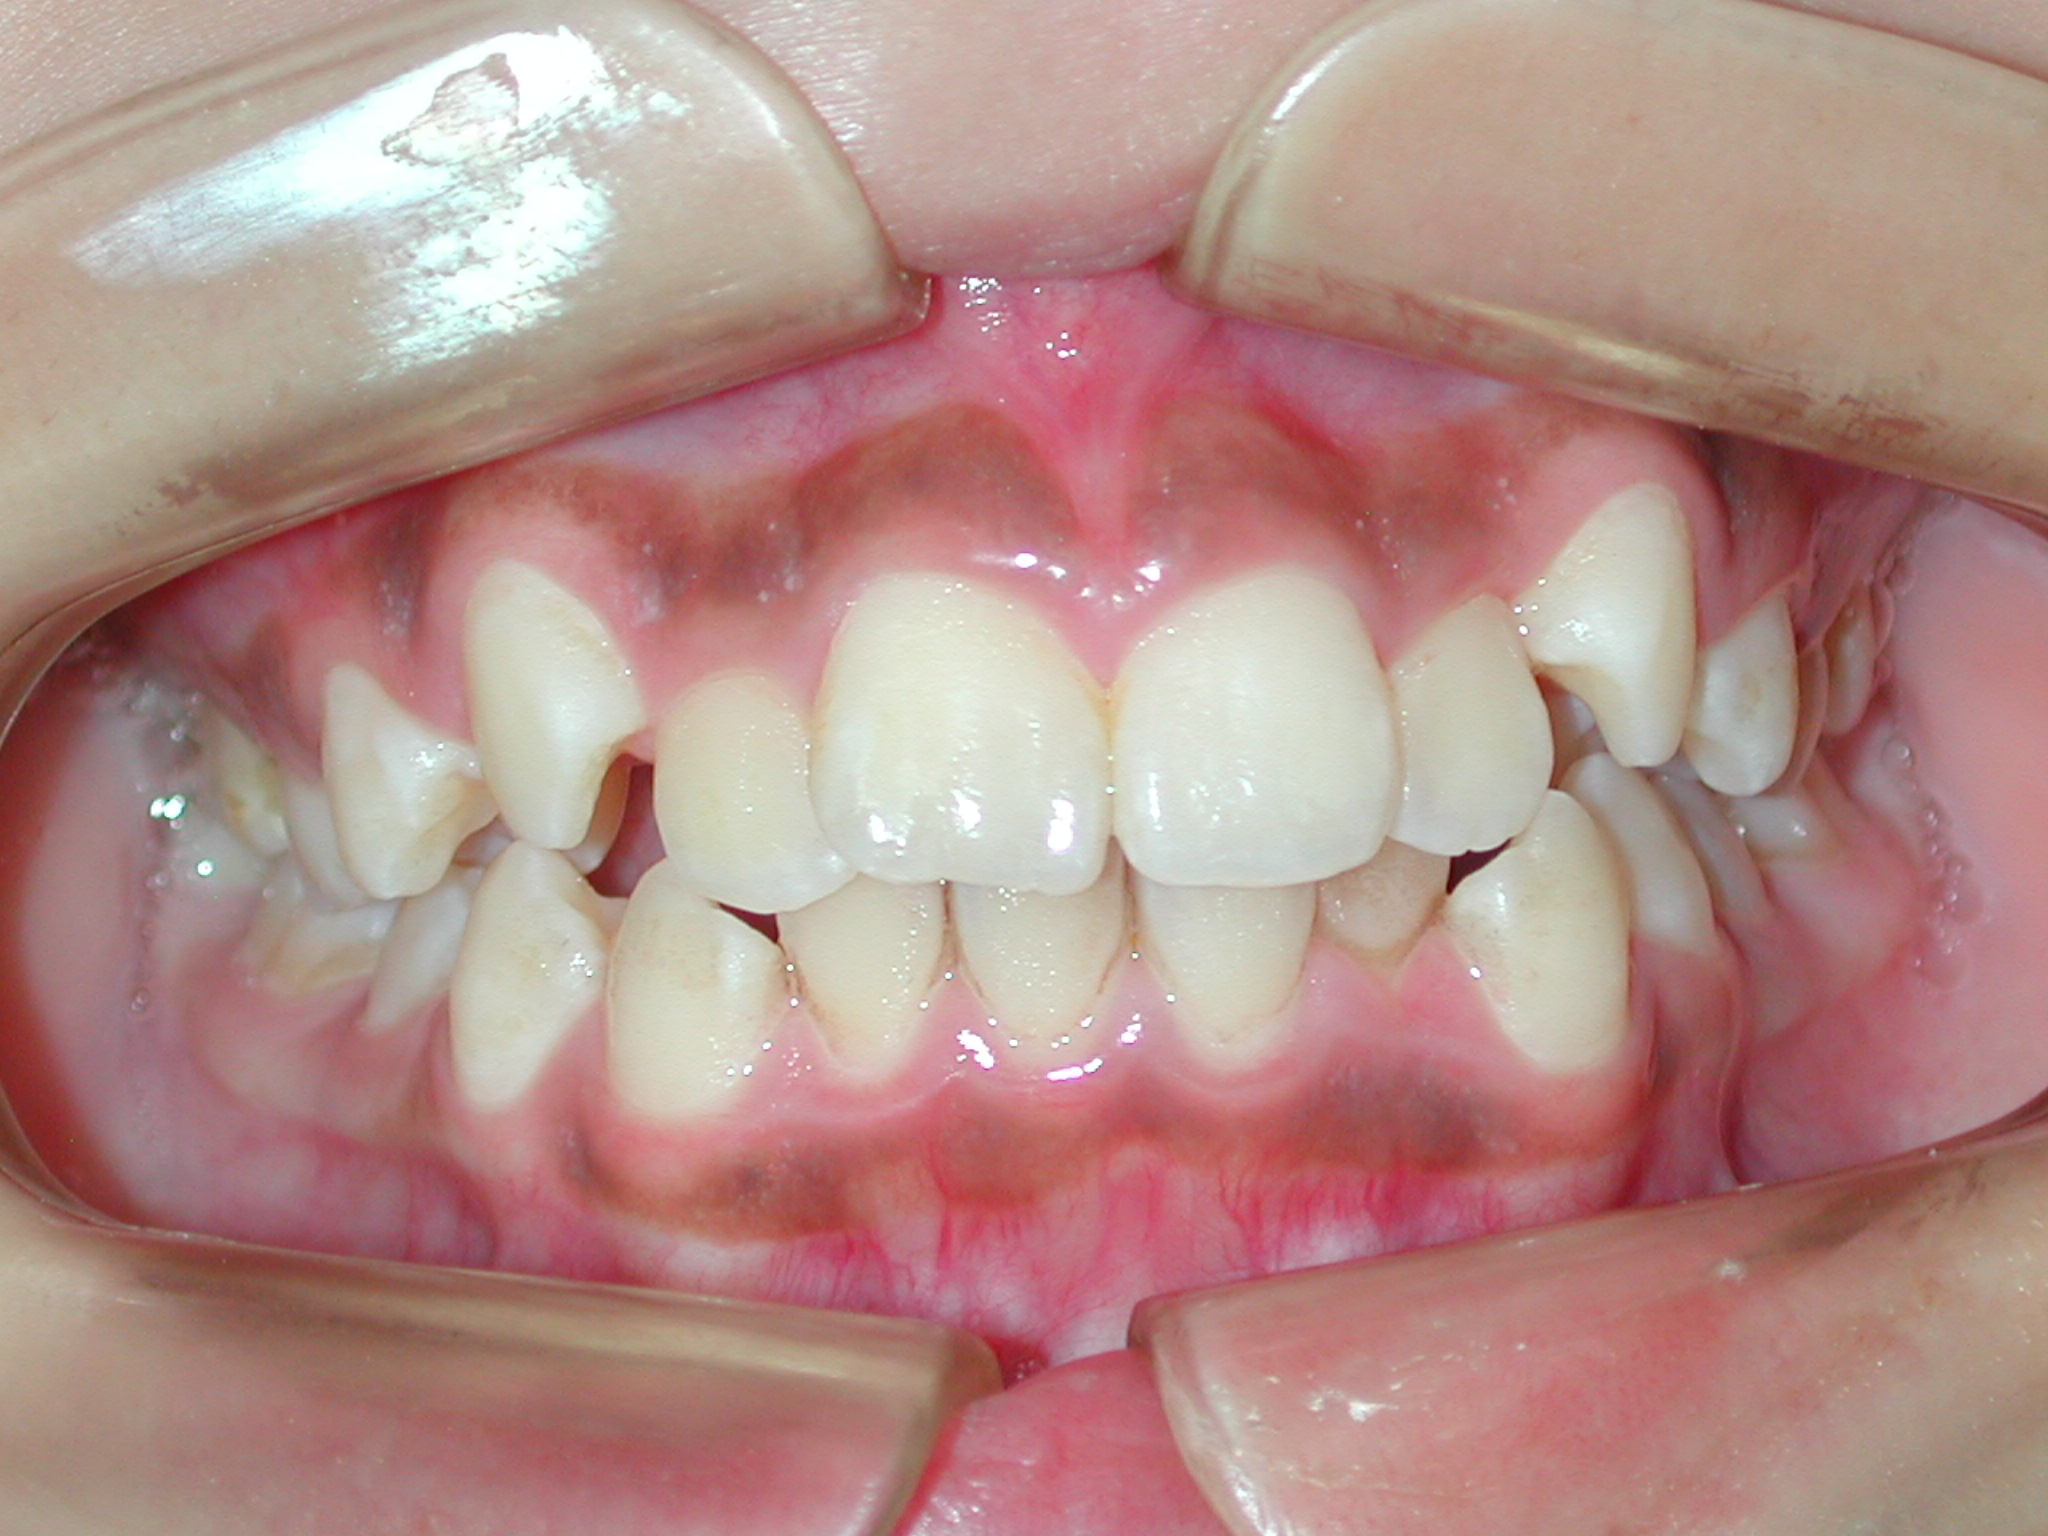

【主訴】10代女性: ご紹介で来院。八重歯とガタガタを抜歯しないで出来るだけ綺麗にしたい。他の歯科に矯正相談に行ったが小臼歯抜歯しないと治せない、抜歯しないと口元がだいぶ出てしまうと言われた。

【治療方法】新素材ゴムメタルを使用したGEAW(ギア)システム用い、小臼歯抜歯なしで治療を行いました。

【矯正治療前】